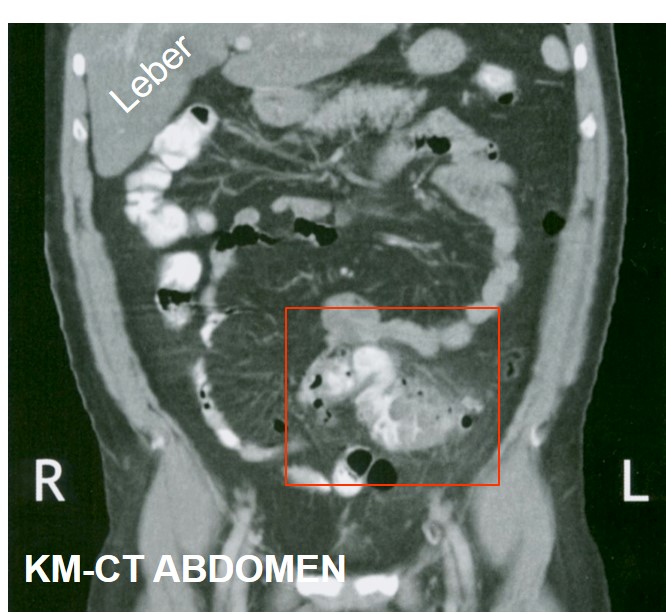

Computertomographie Abdomen

Wandverdickung und Lumeneinengung des Sigma